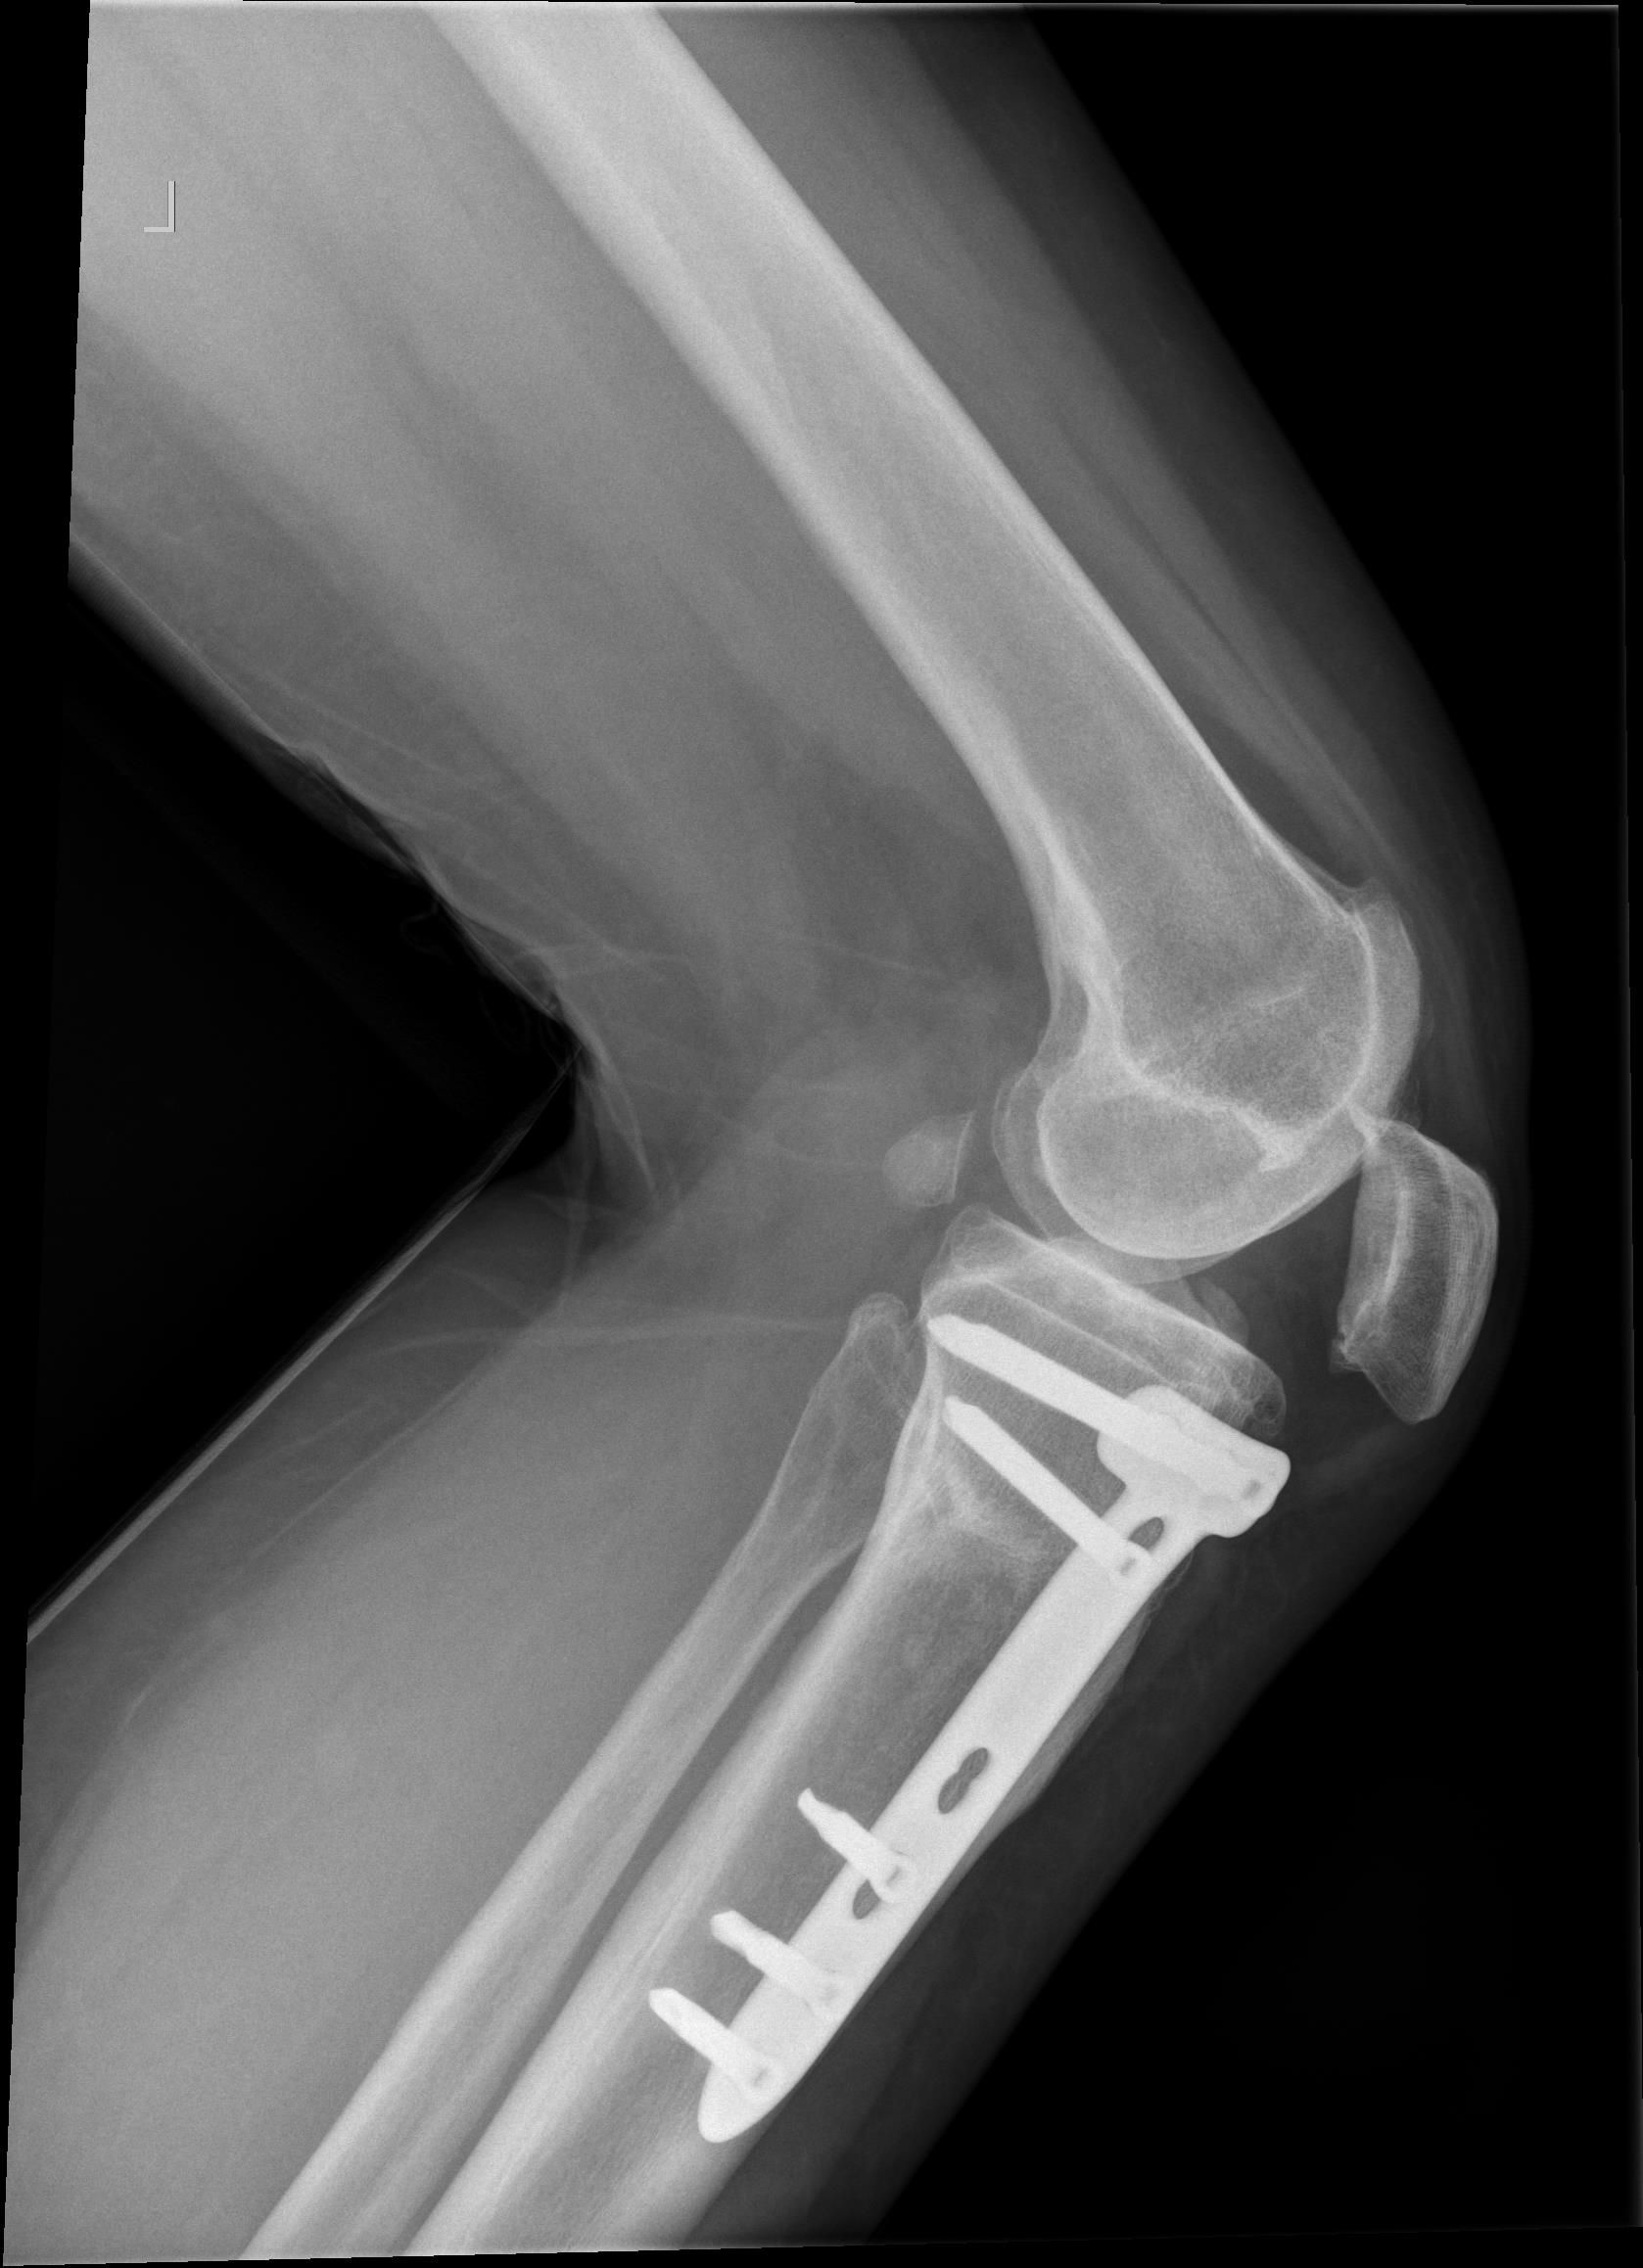

Patient A 53-year-old female patient presented at the emergency department with a locked left knee. The locking occurred whilst sitting in a chair in a flexed knee position. She was unable to unlock her knee due to the pain. On examination the knee was swollen and locked in a 70° flexion angle. An X-ray of the knee showed an inferior patellar dislocation without fractures (figure 1). Six years earlier she was treated with a medial open wedge HTO (OWHTO) with a proximal tuberosity osteotomy with a locked plate for valgus correction of medial compartment osteoarthritis. During surgery a planned 9° correction was performed. Insall-Salvati ratio (ISR) pre-operatively was 0.89. Directly after surgery ISR was 0.83 (figure 2, figure 3). Her postoperative course was uneventful, and the final results were excellent until her recent presentation.

Intervention After administrating analgesics, a reduction was performed by hyperflexing the knee, unlocking the superior patellar osteophyte from the trochlear groove (figure 4.) After two weeks of weight bearing in an extension splint, the patient was advised to resume normal activities. After reduction of the patellar dislocation the X-ray showed an ISR of 0.74. The X-ray also showed a suprapatellar osteophyte.